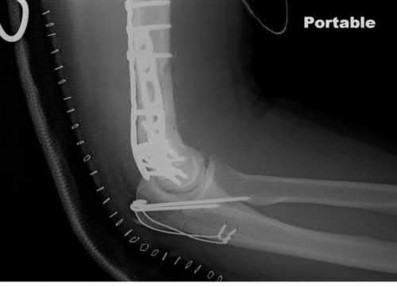

The rare Bosworth fracture-dislocation is a posterior dislocation of the fibula which becomes entrapped behind the tibia. As demonstrated in this vignette, these injuries are extremely difficult to close reduce secondary to the ridge of the posterolateral distal tibia. The irreducible nature of this injury is a known risk factor for the development of compartment syndrome. The CT images further demonstrate fracture extension to the posteromedial rim (“posterior pilon variant”). In this situation, the only effective method to reduce the fracture is through an open posterolateral approach with the interval between the flexor hallucis longus and the peroneal tendons. This is the same approach that is utilized for fixation of the posterolateral fragment and fibula. Loss of dorsiflexion has been demonstrated following this fracture pattern with posterior fixation. The positioning of the plates in Figure F suggests the

utilization of a posterolateral approach.

Figure F: Positioning of the plate suggests a posterolateral approach to address both the fibula and posterior malleolus fractures.